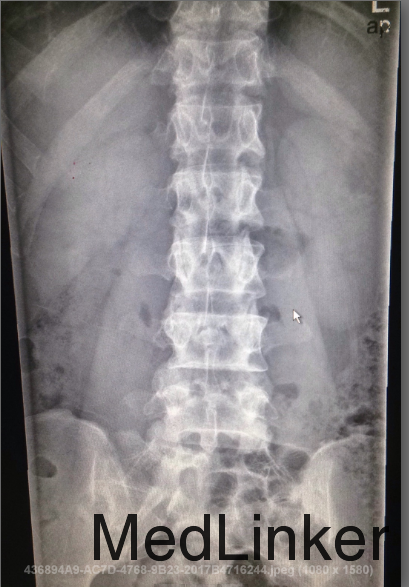

男,27岁,因“反复腰背痛8年余,再发半月余” 患者8余前无明显诱因出现双髂部及腹股沟部疼痛,伴腰背部疼痛,程度较轻。4年余前自觉症状较前加重,久坐后起来时腰痛明显,活动后可缓解,夜间、休息时疼痛明显,逐渐出现翻身、弯腰困难,自觉颈部僵硬,遂就诊于我院门诊,我院门诊诊断“强直性脊柱炎”,服用西乐葆0.2g bid。半月前患者自觉腰背痛发作频繁,服用西乐葆治疗后可缓解,但效果不佳,现为进一步来我院。患者今日有咳嗽,咳痰少,无发热,近l周有腹泻,小便正常。体重无明显变化。

T:36.8℃,P:73次/分,呼吸:18次/分,血压:114/61mmHg。神清,对答切题,查体合作,心肺听诊未见异常,全腹无压痛、反跳痛,腰椎前后方向活动受限,骶髂关节椎旁肌肉压痛阴性,腰椎无偏曲,枕墙距4cm,耳壁距12cm,胸廓扩张3cm,Schober试验:移动距离2.5cm,骨盆按压试验阴性,4字征阳性,四肢关节无红肿、压痛,双下肢不肿。 脊柱x线片提示:符合强直性脊柱炎改变。

诊断:强直性脊柱炎 治疗:入院后予止痛治疗,予生物制剂恩利治疗。